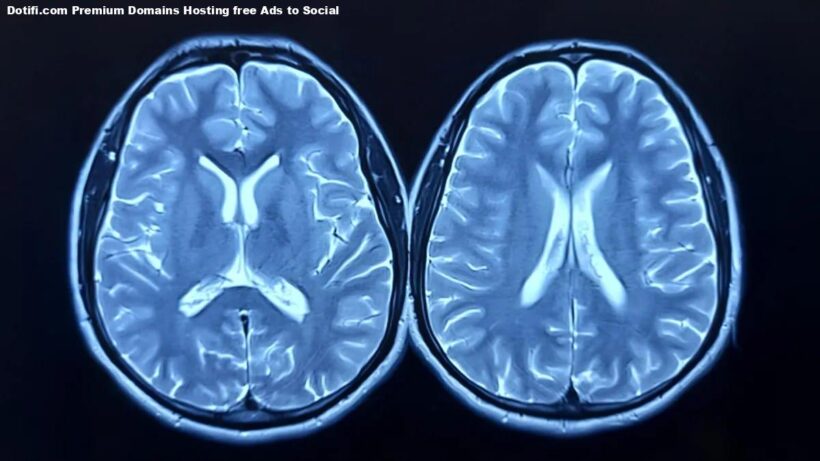

The research team looked at longitudinal brain scans from nearly 1,000 healthy adults, taken as part of the UK Biobank study. Some participants had scans before and after the pandemic; others, only before.

Using advanced imaging and machine learning, the researchers estimated each person’s “brain age” — how old their brain appeared to be compared to their actual age.

The brain age model was developed using brain scans from over 15,000 healthy individuals, without comorbidities, allowing the researchers to build an accurate model for estimating brain age.

Stamatios Sotiropoulos, Professor of Computational Neuroimaging, and co-lead author added: “The longitudinal MRI data acquired before and after the pandemic from the UK Biobank gave us a rare window to observe how major life events can affect the brain.”